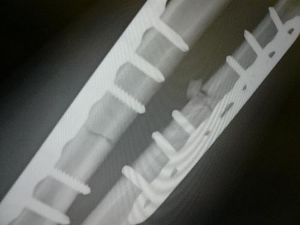

3.X線攝片可明確骨折和移位元情況。

受傷後,前臂出現疼痛,腫脹、畸形及功能障礙。檢查可發現骨末殘音及假關節活動,骨傳導音減弱或消失,X線拍片檢查應包括肘關節或腕關節,可發現骨折的準確部位,骨折類型及移位方向,以及是否合併有橈骨頭脫位或尺骨小頭脫位,尺骨上1/3骨幹骨折可合併橈骨小頭脫位,成為孟氏骨折。橈骨幹下1/3骨折合併尺骨小頭脫位,成為蓋氏骨折。